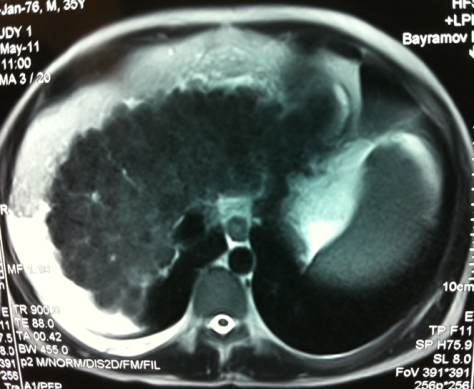

- Diaqnozu dəqiqləşdirmək üçün Qc venaları yoxlanılmalıdır. Bunun üçün dopler USM, KT-angioqrafiya, MRT-angioqrafiyalar və ya kontrastlı venoqrafiya edilir.

- Görüntüləmədə Qc venalarının trombotik tutulması diaqnozu dəqiqləşdirən əlamətdir.

Baddi-Kiari sindromu böyük qaraciyər venalarının tıxanması nəticəsində meydana gələn venoz durğunluqdur, qaraciyər venaları ilə yanaşı aşağı boş venada da tıxanma ola bilir. Tromboz, fibroz, membran və infiltrasiya (şişlər, iltihab) ən çox rast gələn səbəbləridr. Erkən mərhələlərdə kəskin hepatit və kəskin qaraciyər yetməzliyi, xroniki mərhələdə sirroz və PH meydana gələ bilir. Diaqnozu üçün tomoqrafiya və kontrastlı angioqrafiya lazım gəlir, Qc venalarının trombotik tutulması diaqnozu təsdiqləyir. digər xarakterik əlaməti birinci seqmentin hipertrofiyasıdır. Erkən mərhələdə dekompressiya (cərrahi və stend) sirroz əmələ gəldikdə isə transplantasiya ön planda tutulur.

Qaraciyər venalarının görünməməsi, kontrastlaşmaması və ya trombla tıxanması.

- Görüntüləmədə qaraciyər venalarının tıxanması, I seqment hipertrofiyası ola bilər (xroniki forma);